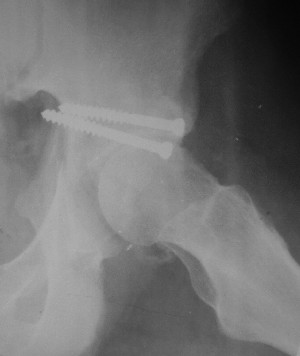

Контрольный снимок перед разрешением нагрузки прямой 13/10/03

|

Перед разрешением нагрузки боковой 13/10/03

Два месяца нагрузки без костылей 19/12/03

Еще месяц 20/02/04

После протезирования прямой 5/04/04

После протезирования боковой 5/04/04

Больной 18 мая 2003 года в автоаварии получил перелом левой вертлужной впадины, вывих бедра. Госпитализирован в один из стационаров области.Вывих вправлен. В последствии бедро вывихивалось еще дважды. На консультацию был представлен снимок от 19.05.03г., больной переведен к нам 3.06.03г. Снимок при поступлении - перелом впадины, задне-верхний вывих бедра. 05.06.2003 г. выполнено открытое вправление вывиха левого бедра и остеосинтез стенки вертлужной впадины двумя винтами. Послеоперационный период без осложнений. Объем движений в левом тазобедренном суставе восстановился полностью. Выписан на амбулаторное лечение в удовлетворительном состоянии с рекомендациями 3 месяца ходить на костылях без нагрузки на оперированную конечность. На контрольных рентгенограммах левого тазобедренного сустава 13.10.2003 г. - признаки консолидации перелома; плотность, форма головки и состояние суставных поверхностей удовлетворительные. Разрешена дозированная осевая нагрузка, на конечность с использованием дополнительной опоры. 19.12.2003 г. больной обратился с жалобами на боли в левом тазобедренном суставе. На рентгенограммах левого тазобедренного сустава 19.12.2003 г., 20.02.04г. - асептичекий некроз головки бедра. 5.04.04г. - эндопротез. Сейчас ходит без трости, не хромает. Особенность эндопротезирования - при удалении винтов прослежена линия перелома заднего края впадины и предложено установить чашку несколько меньшего диаметра, чтобы она была покрыта несломанной частью.